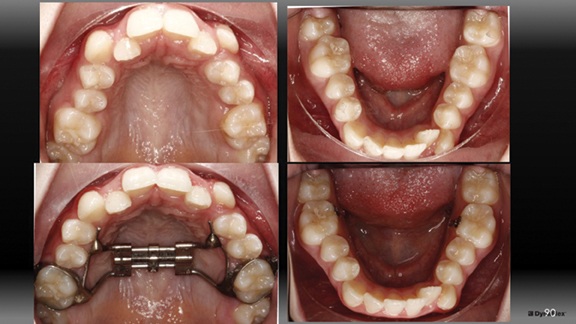

We initially began with an RPE. Caplin hooks were bonded to the lingual of the L6s and nighttime 3/16 heavy elastics were worn from these hooks to the buccal hooks of the U6s to upright the L6s to keep track with maxillary expansion. I have written much about this technique previously (Fig. 5).

Figure 6 shows progress records midway through her treatment after braces were bonded. Bite turbos were placed posterior on the molars because I wanted to limit any vertical increase in this case as that would have the potential of further decreasing chin prominence. Posterior bite turbos used to limit molar eruption and clockwise mandibular rotation are quite important in chin-deficient patients. Upper incisor brackets were not flipped to reverse torque in this case as I desired the upper incisors to roll forward a bit like we discussed earlier. Approximately 0.3 mm of IPR was performed at each contact canine to canine in both arches.

The Architects of the Lips: Part 4

Fig. 5

Fig. 6